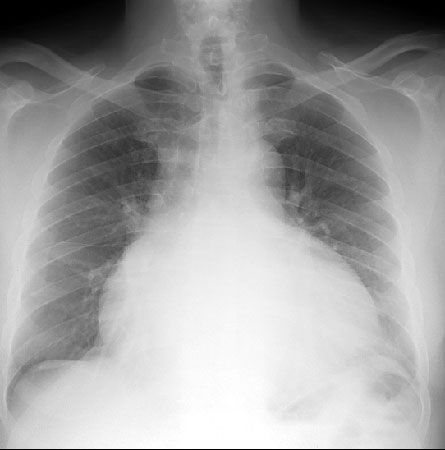

• Рентгенография грудной клетки.

- Рентгенологическое исследование грудной клетки: на снимке четко визуализируется увеличение тени сердца и застой в легких.